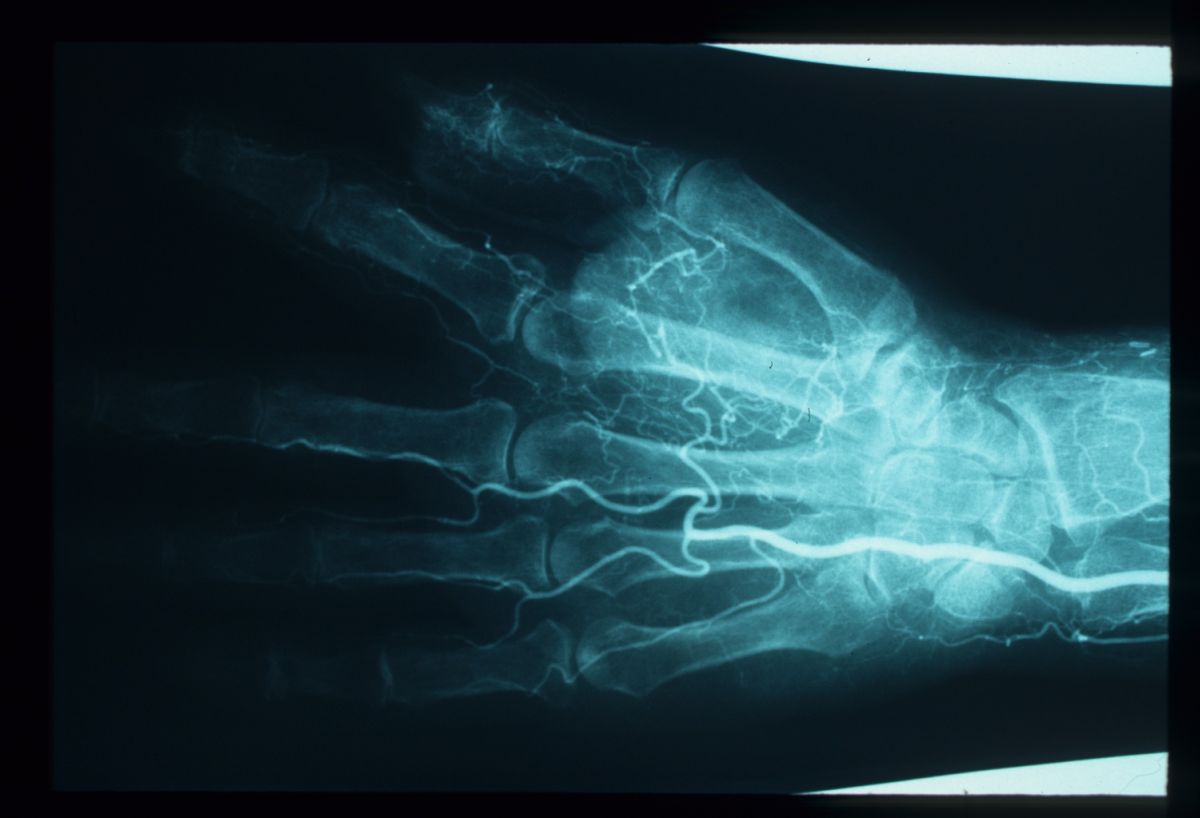

| Case 2. This patient developed

ischemia of the radial aspect of her left hand during a carotid

endarterectomy. These pictures were taken four weeks postop. |

| Imaging demonstrated

nonreconstructible vascular disease. |